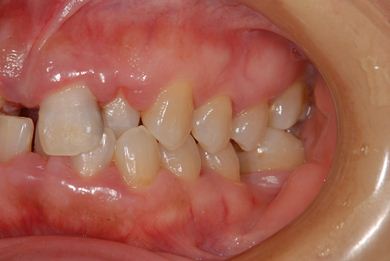

| 性別/年齢 | 女性 / 52歳 | ||||||||||||||||||||||||||||||||

| 主訴 | 歯周病で歯の位置がずれてしまった。 | ||||||||||||||||||||||||||||||||

| 治療内容 | インプラント2本(抜歯即日スピードインプラント)、メタルボンドセラミッククラウン4本 | ||||||||||||||||||||||||||||||||